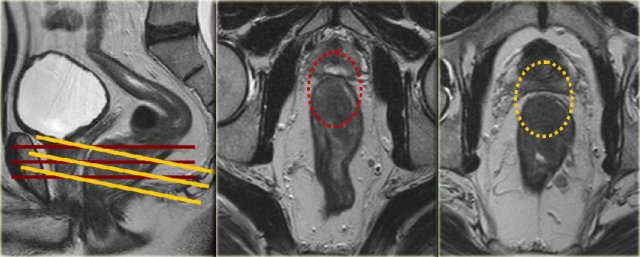

Example showing

impact of sequence angulation:

In the middle

image the axial view is angled in true axial plane, which is not perpendicular to the tumor axis of this low rectal tumor.

This resulted in the false impression that the MRF was involved on the anterior

side (red circle).

In the right image, the axial view is correctly planned

perpendicular to the tumor axis and it was clear that the MRF was not involved

(yellow circle).